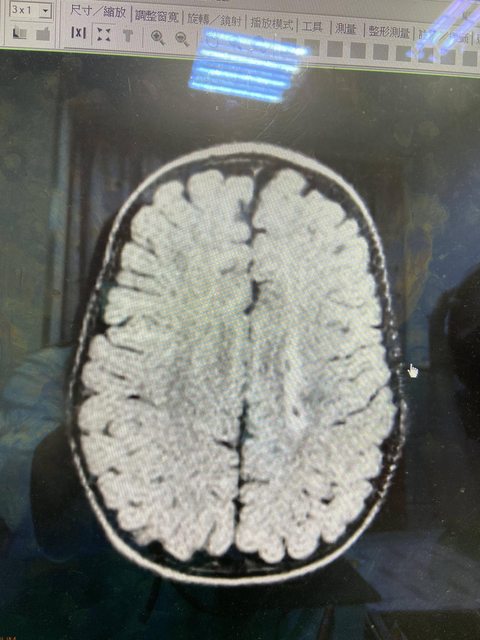

標題下的有點恐怖,板上好像也沒有相關文章,想把二寶的狀況分享給大家 二寶懷孕過程一切正常,有做羊膜穿刺、羊水晶片,高層次也都ok 37週整迫不及待的出生(剖腹產),出生一個月時照腦部超音波檢查,發現有兩側腦室不對稱的狀況,醫生說等長大一點再追蹤,當時上網查這狀況好像不是很嚴重?就沒有再多想 八個月大時,還沒辦法獨立坐穩,於是在家裏積極的練習坐姿(背後幫他撐著),九個月大時終於可以獨立坐穩。因為是送托嬰,老師也提醒二寶的右手右腳都「不太喜歡動」、「只用左手抓東西」、「爬行也都無法撐起」、「肚子貼地爬」,且前進時只會用左腳輔助,建議我們給醫生看一下 掛了馬偕的小兒復健科,醫生覺得有肌張力過高問題,診斷證明寫發展遲緩,安排復健課程,但小朋友的復健真的好難排,醫院至少要等半年,找了家裡附近的復健科,也是排了三個月才終於在前幾天上到第一次課 同時間我們掛了小兒神經科,醫生看到當時的超音波檢查報告,也幫我們再照了一次超音波(當時11個月大),發現左腦室有一個凹陷處,立刻安排三個禮拜後照核磁共振檢查 等到今天終於看到報告,發現左腦室有白質軟化症狀(醫生在診間是說「液化」) 醫生很溫柔的跟我們說 「MRI看起來,左腦有受過傷,還有殘留的血塊,這個發生的原因不明,白白的那塊叫做白質液化,在醫學上定義是腦性麻痺,但不用被這四個字嚇到,腦麻也是有非常輕微的。這塊損傷的神經不會恢復,所以右半身的大肢體動作會被影響,要持續的復健,建立肌肉記憶,看能不能補足,接下來定期回診觀察,目標追上其他小孩的進度」 https://i.imgur.com/rnjqk8V.jpg

看診完的心情有點複雜 不幸的是二寶真的有不可逆的腦傷,未來運動什麼的一定會受到影響…嗚嗚,媽媽沒有給你健康的身體 但不幸中的大幸是,二寶找到明確病因,而且腦部損傷不算太嚴重,只要積極復健,是有機會追上一般小朋友的! https://i.imgur.com/EXIUlzd.jpg